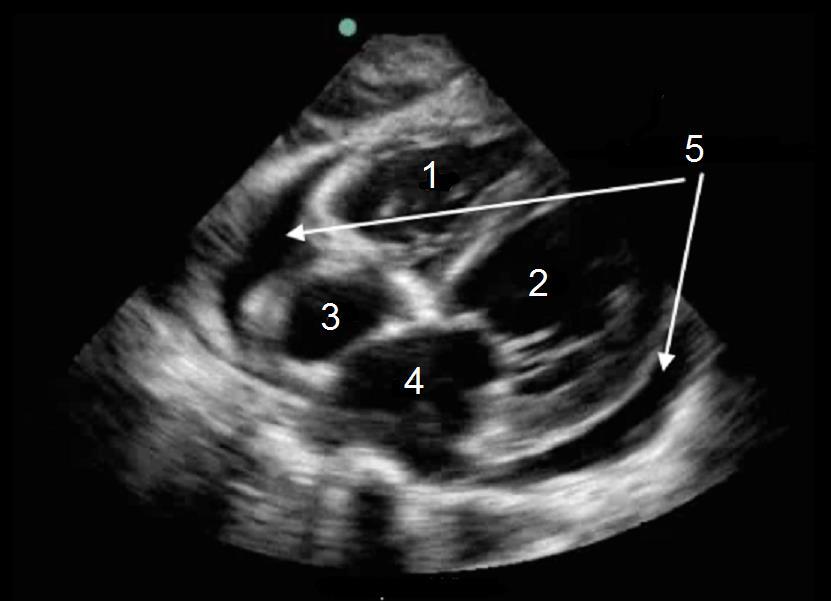

1. Right Ventricle (RV)

2. Left Ventricle (LV)

3. Right Atrium (RA)

4. Left Atrium (LA)

5. Pericardial Fluid (Effusion)